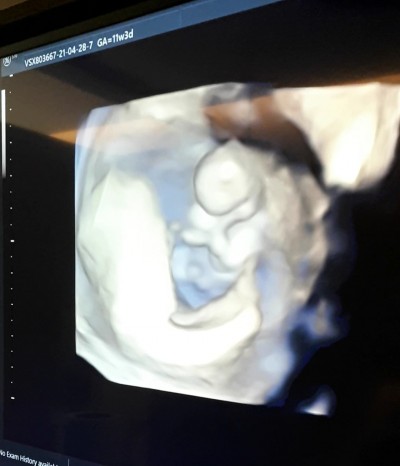

Tecrubeli anneler cinsiyet tahmini yapabilirmisiniz:)

Gebelik haftası 11+3

Kapatılma nedeni: Cinsiyet tahminlerini sol üst köşeden konu dışı sohbetten sorabilirsiniz

Bu sekilde anlasilmio canim.bak benimkinin ayni gun siyah beyaz ultrasyonuna :) daha tahmin yurutulur oluyor